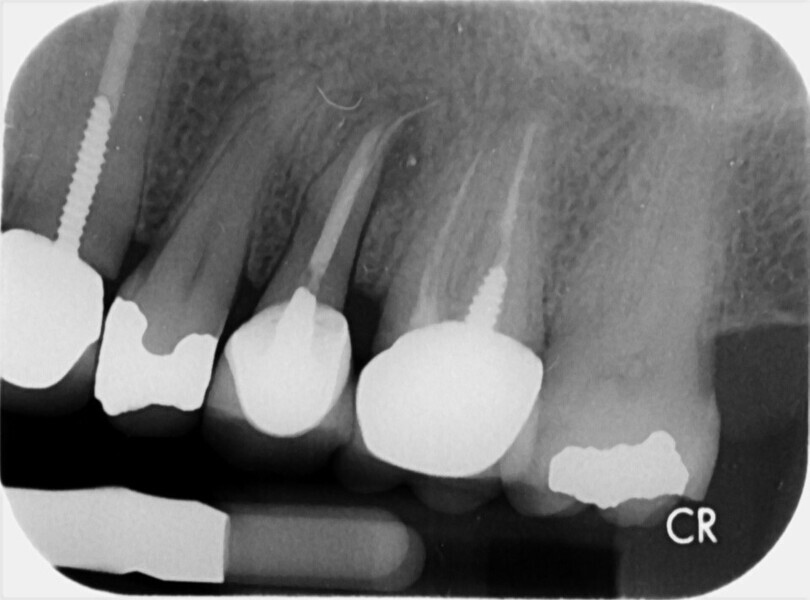

Buccal root of the bifurcated maxillary premolar—a danger zone during root canal therapy